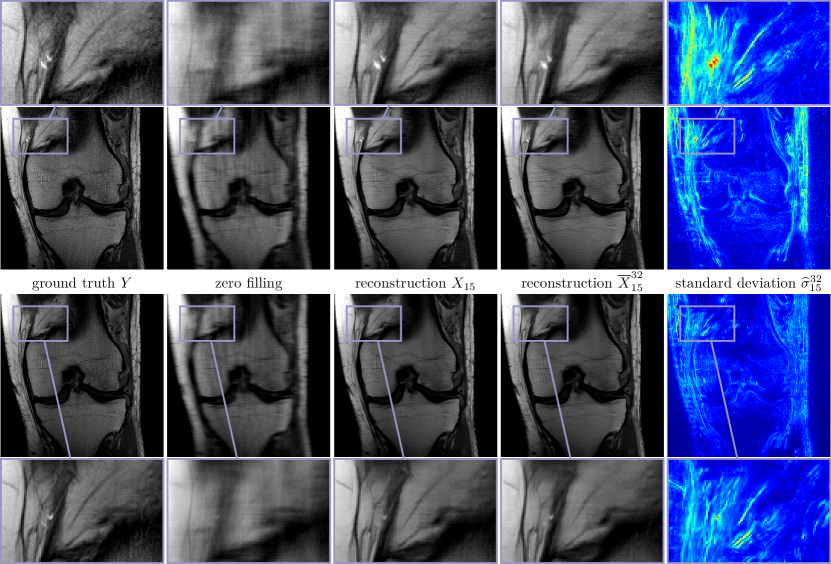

Figure 6 shows the multi-coil reconstruction results for 888-fold undersampling and both data sets in the same arrangement as before, the entropy level is H¯(Σ)=31.41¯𝐻Σ31.41\overline{H}(\Sigma)=-31.41. As expected, the overall reconstruction quality is quantitatively and qualitatively inferior to the case R=4𝑅4R=4. As before, the difference of the deterministic and the stochastic restored images is relatively small and the standard deviations properly identify regions with higher uncertainties. Finally, Figure 7 depicts zooms of two different MRI reconstructions (R=4𝑅4R=4, PD), in each row the ground truth, two realizations, the stochastic reconstruction and the standard deviation are visualized. The regions highlighted by the arrows indicate structures and patterns that differ among various samples. The variability of the single realizations can be interpreted as hallucinations, which are properly detected in the corresponding standard deviations. This empirically validates that our proposed method to measure the standard deviation actually quantifies the magnitude of the model-related uncertainty. Figure 8 contains a visual comparison of our method with selected competitive methods from the fastMRI leader board. As a result, both E2EVN [42] and iRim [38] achieve slightly superior quantitative results at the expense of significantly more learnable parameters. In a qualitative comparison, we observe that our proposed method is capable of retrieving fine details, only the signal of a few high-frequency patterns is lost. Finally, U-Net [23] results are inferior to the considered competitive methods – both quantitatively and qualitatively.

Figure 6: Multi-coil MRI reconstruction results for PD (first row) and PD-FS (second row) data and R=8𝑅8R=8. From left to right: ground truth images Y𝑌Y, zero filling, deterministic reconstructions X15subscript𝑋15X_{15}, stochastic reconstructions X¯1532superscriptsubscript¯𝑋1532\overline{X}_{15}^{32} and standard deviation σ^1532superscriptsubscript^𝜎1532\widehat{\sigma}_{15}^{32} (00 Refer to caption 0.020.020.02).

Figure 8: Visual comparison of selected MRI reconstruction methods for PD (first row) and PD-FS (second row), both with R=4𝑅4R=4. From left to right: E2EVN, UNet, iRim, TDV(deterministic), TDV(stochastic).